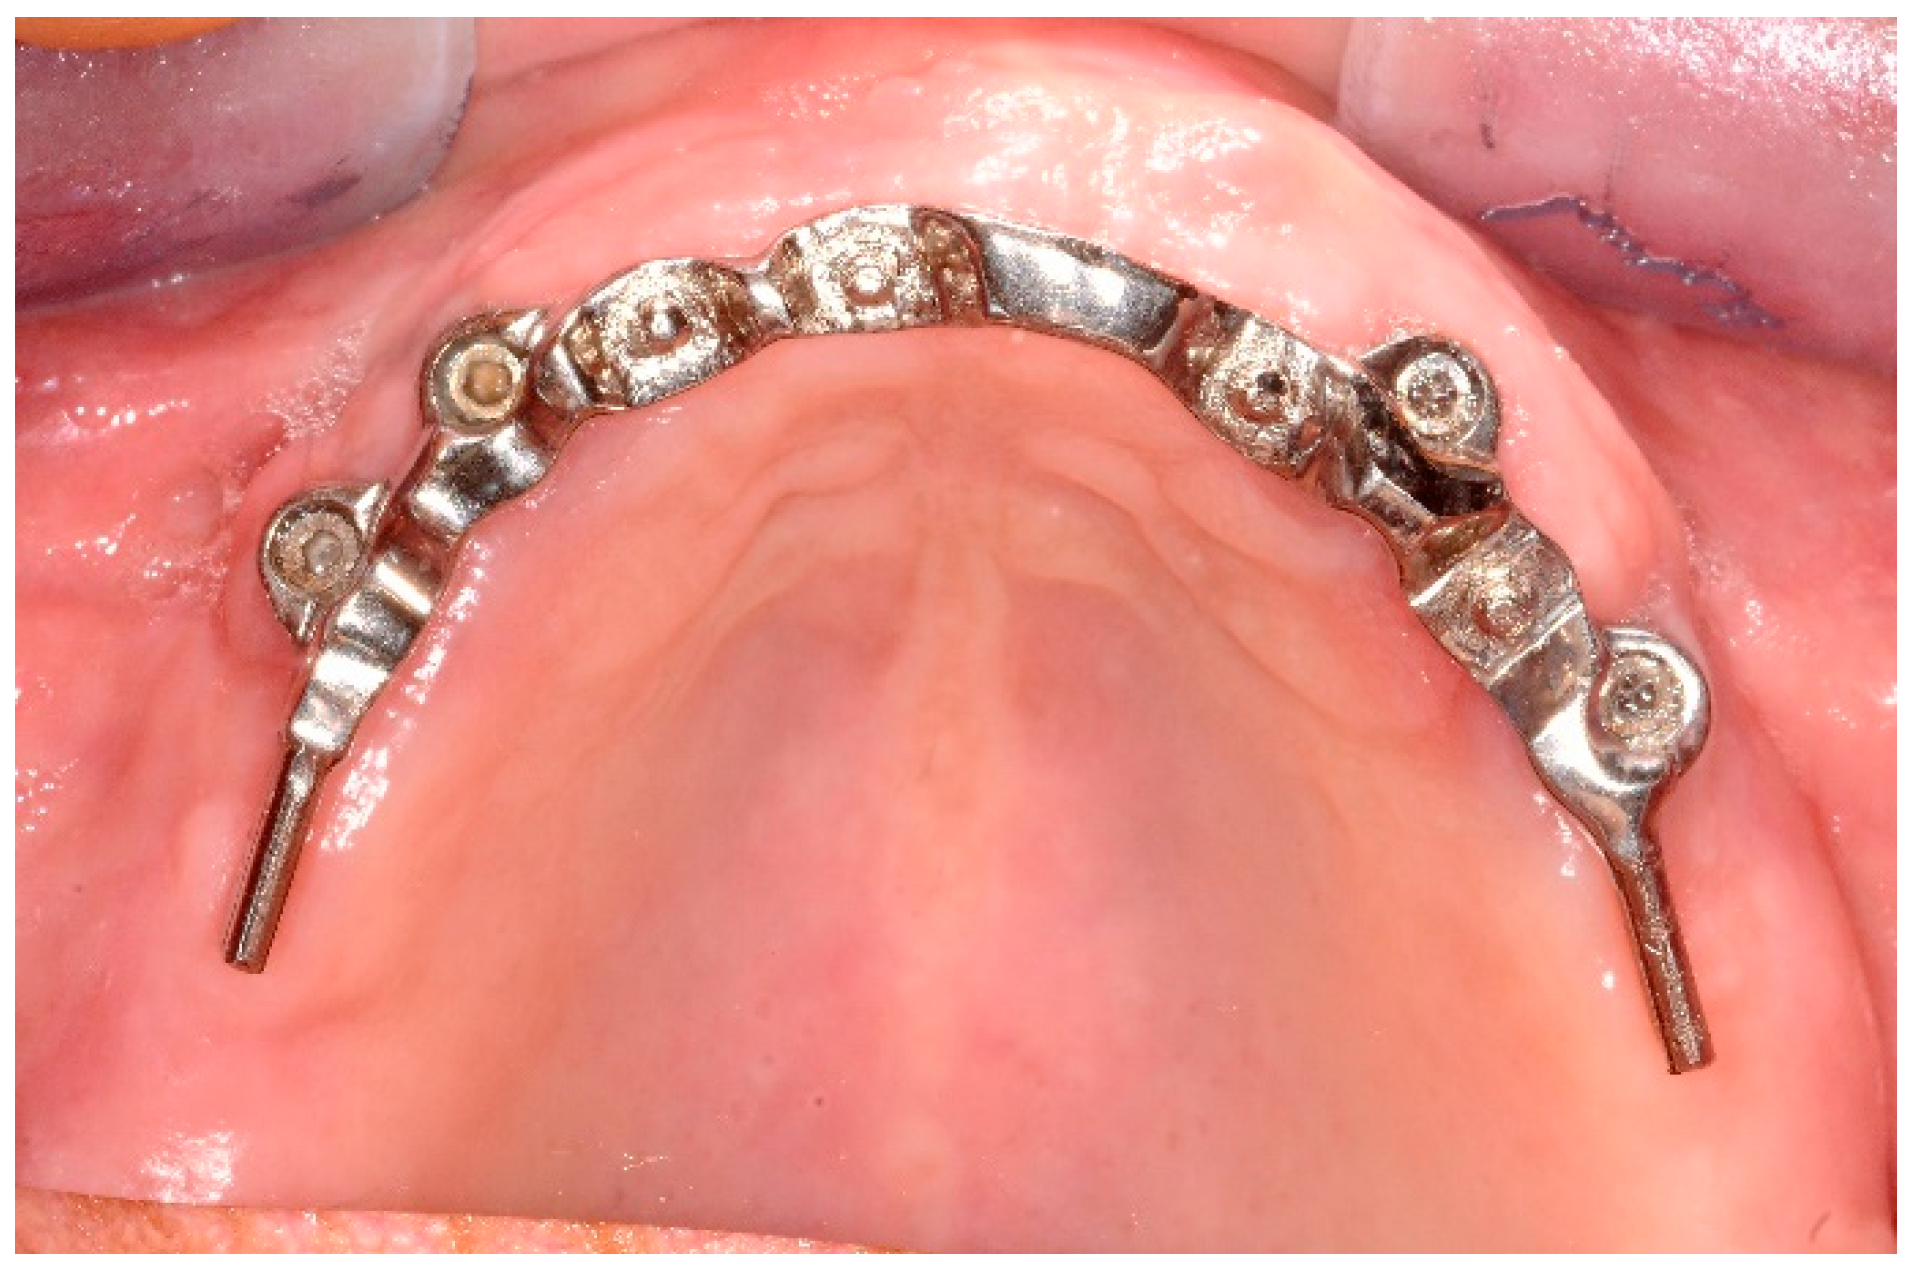

Patients were rehabilitated with both implant-retained or -supported overdentures. In case of implant-retained overdentures, pre-existing or a new developed complete removable dentures were used followed standardized techniques [25]. Implant-retained overdentures were delivered on 1 to 5 unsplinted implants. The following attachment systems were used: Equator attachments (OT Equator, Rhein83, Bologna, Italy), ball attachments (OT Cap, Rhein83), or Locator attachments (Zest Dental Solutions, Carlsbad, CA, USA) (Figure 1, Figure 2, Figure 3 and Figure 4). The Rhein83 OT Equator is a low profile castable and direct implant overdenture attachments with a low vertical profile of 2.1 mm and diameter of 4.4 mm. This system offers multiple solutions for overdenture treatment planning when vertical space limitations are a consideration.

Figure 2. Ten-year follow-up of maxillary overdenture with castable attachments.